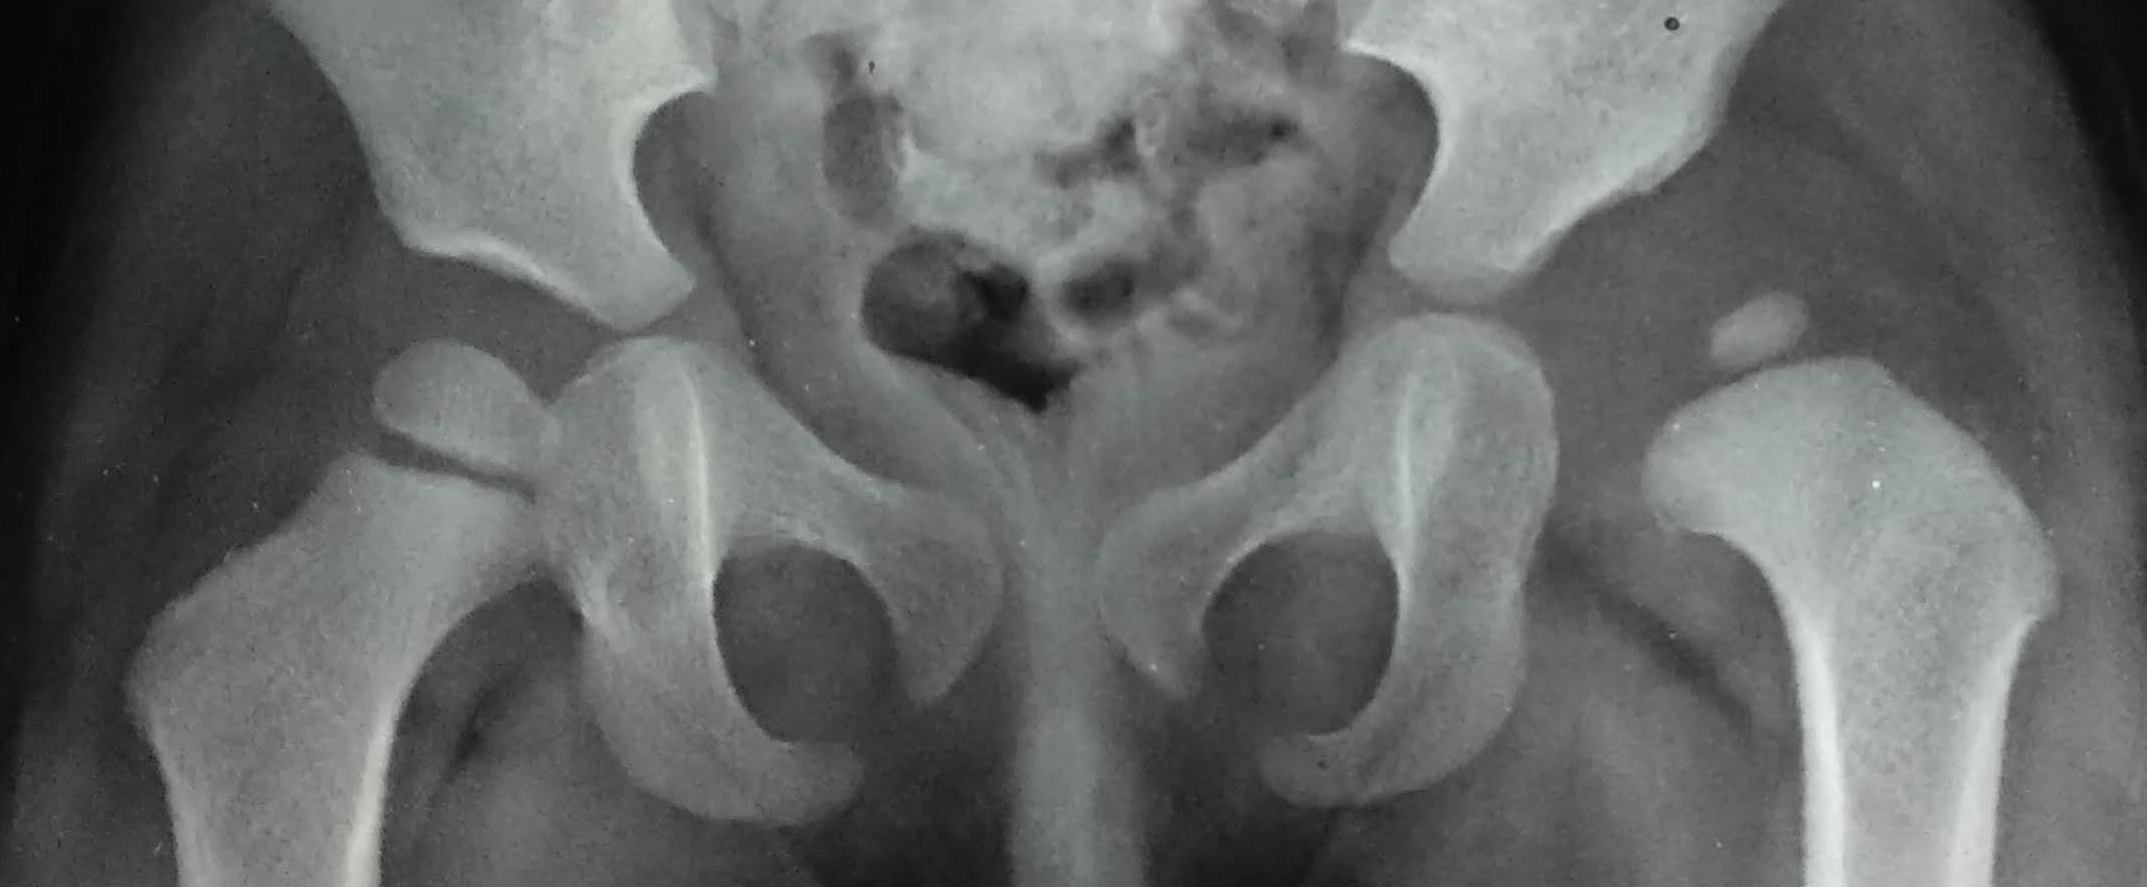

The state of hip before the osteotomy. Open reduction was done elsewhere about a year ago. Persistent hip dysplasia was observed.